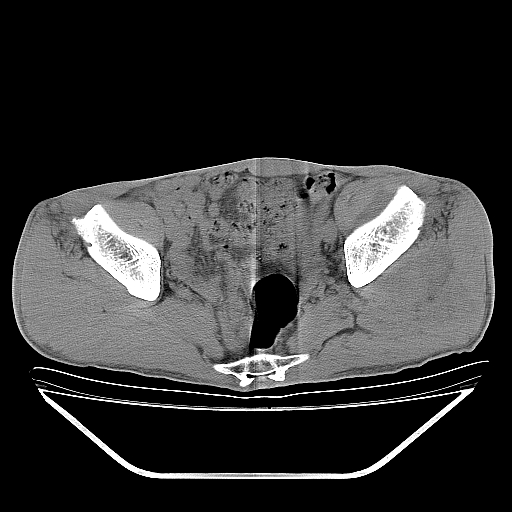

以下是引用天南地北在2007-10-4 18:01:00的发言:[br][br]考虑左髂部恶性肿瘤(溶骨性骨质破坏+软组织肿块影+残留骨质);以滑膜肉瘤可能性大。[br]建议穿刺活检

以下是引用liuyue在2007-10-4 23:38:00的发言:[br]左髂部恶性肿瘤,建议穿刺活检,或先做肺部检查,除外肺癌转移之可能。